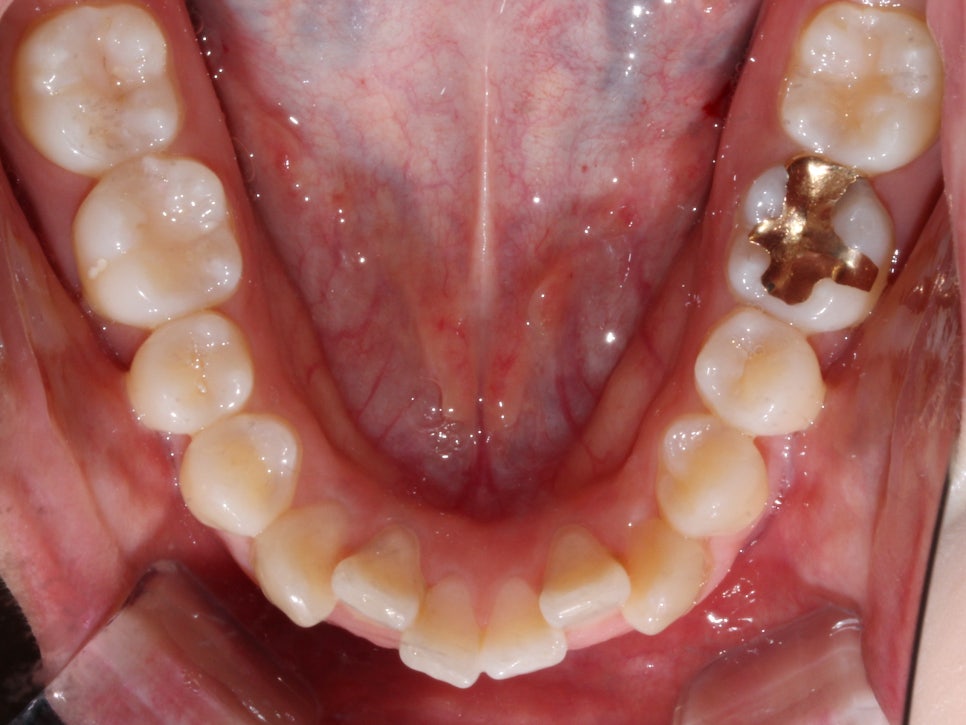

상악과 하악의 교합면이 고르지 못하고

덧니로 인해 치열에 총생이 생겨

심미적으로 좋지 못한 상태입니다.

하악의 경우 덧니로 인해 치아 사이의 공간이

매우 좁아 전치부의 치아가

삐뚤빼뚤해 보이기까지 합니다.